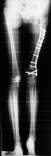

Pre Op

X-ray (Left femur)

osteolytic lesion

(?) osteosarcoma

Post Op

Graft taken well

1cm shortening

of left femur

ROM : 0- 110’